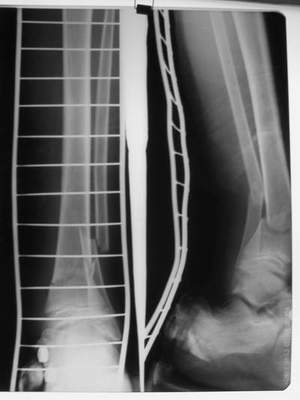

в гипсе

Промежуточный

В пределах 2 см.

Не катастрофа. Рост продолжается, будем следить в динамике.

Это сросшийся перелом малоберцовой кости. И ложный сустав

н\3 б\берцовой кости.